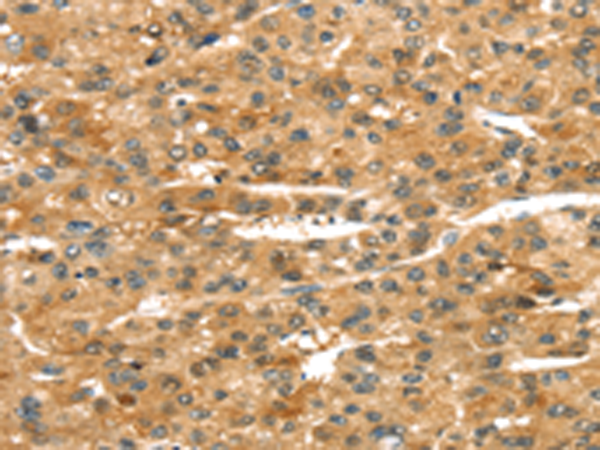

分类: 科研抗体货号: P08739别名:应用: WB,IHC反应种属: Human